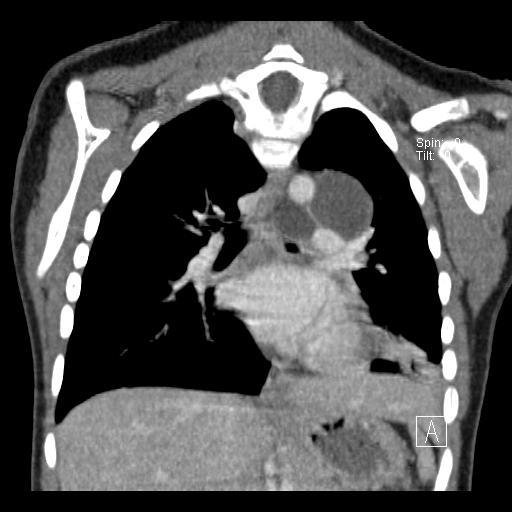

Duplications are congenital malformations thought to arise from disturbances in embryologic development. Multiple theories have been postulated to account for their development. Bentley and Smith proposed that the primary defect was the development of a split notochord that allowed the connection between the yolk sac endoderm and the ectoderm and that subsequent duplication of the gut resulted from eventration of the yolk sac between the halves of the vertebra. It is usually diagnosed by its compression symptoms and radiologically confirmed by a CT scan or MRI.